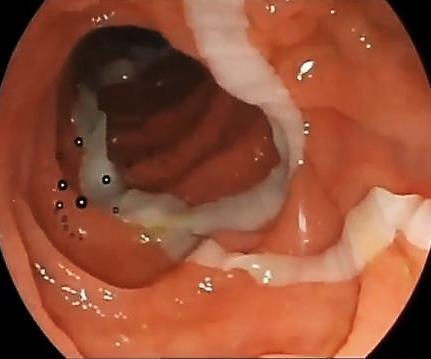

Imagens endoscópicas de uma Taenia saginata no jejuno proximal (à esquerda) e de múltiplos

Ascaris lumbricoides obstruindo o piloro (à direita).